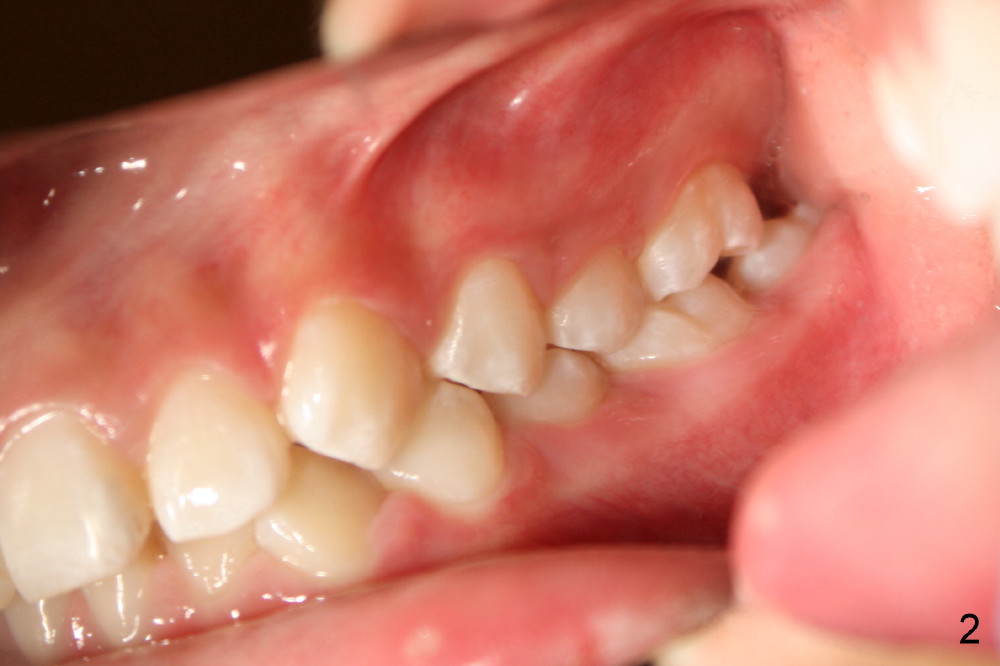

Joshua, 11 years old, has dental crowding (Fig.1), particularly in the lower arch (Fig.3) with molar Class I relationship (Fig.2). The lower 5s rotate (Fig.2 black lines), which are corrected with power chains (Fig.4,5) after bracketing and placing .012" niti wires (Fig.6).